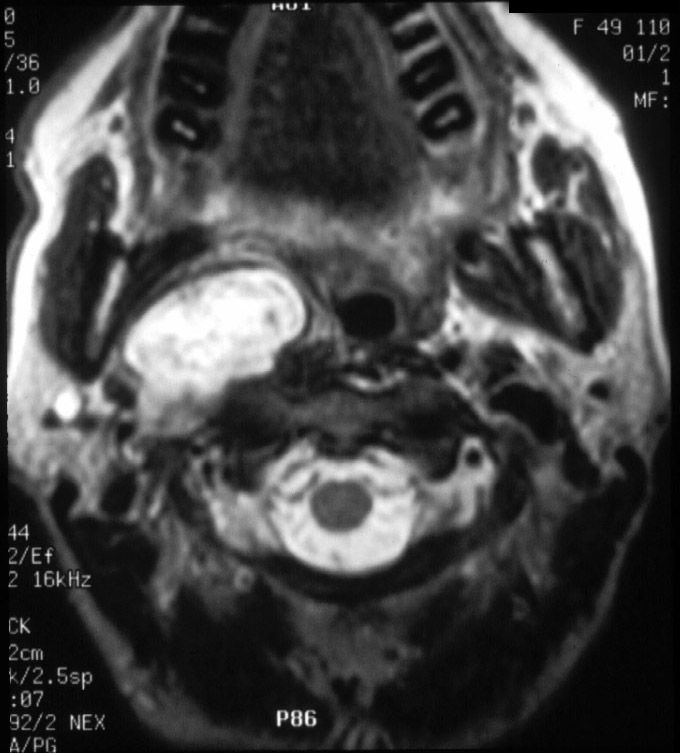

Axial MRI illustrates a right parapharyngeal space lesion.